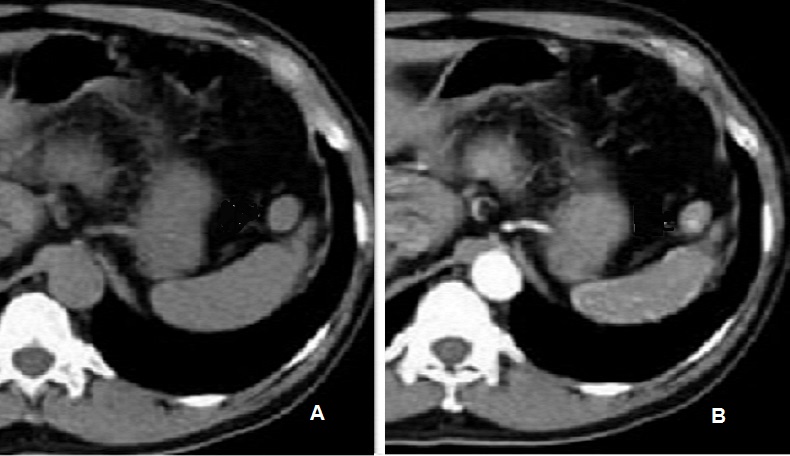

Image radiologique TDM en

coupe axial d'une rate surnumeraire multiple au bord

anterieure de la rate . Aspect lesionaire est

deux nodules isodensite nette et lisse situe a

bord anterieure de la rate principale ( A ) . Sur

les exposes avec contrast intraveineuse ( B ) elles

se rehaussent heterogene a precoce et puis homogene

au temps d'evacuation |